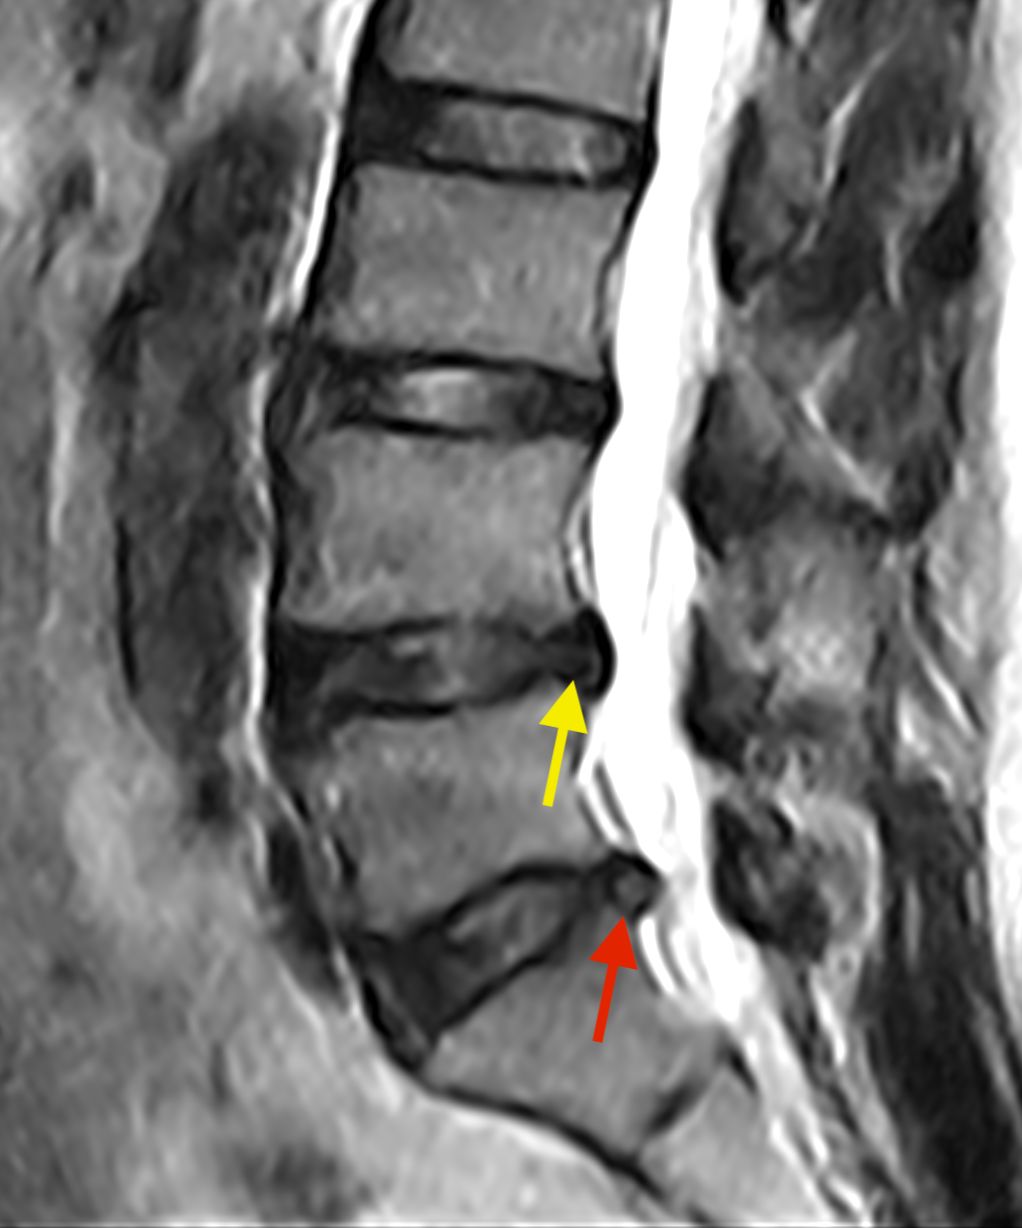

Dopo la laurea e la specializzazione in Neurochirurgia con lode presso il Policlinico Agostino Gemelli, ho dedicato la mia formazione esclusivamente alla cura delle malattie della colonna vertebrale e del midollo spinale, come ernie del disco, stenosi del canale vertebrale, spondilolistesi, metastasi vertebrali e tumori del midollo spinale, attraverso esperienze presso centri di riferimento italiani ed internazionali e a numerosi corsi e master di II livello.

Queste patologie si manifestano con sintomi neurologici (ad esempio: dolore o perdita di forza ad un arto, formicolii, rigidità o perdita di coordinazione alle mani o durante la marcia) oppure con sintomi meccanici (ad esempio: mal di schiena prevalente durante il movimento). Una valutazione specialistica deve mirare a correlare i sintomi clinici con le alterazioni presenti alle immagini radiologiche, ed a guidare il paziente attraverso il percorso di cura, finalizzato al recupero della sua ottimale qualità di vita.

Mi occupo delle seguenti patologie:

• Patologie degenerative della colonna:

• ernia del disco cervicale, toracica e lombare;

• stenosi del canale vertebrale cervicale e lombare;

• mielopatia cervicale spondilogena;

• spondilolistesi cervicale e lombare;